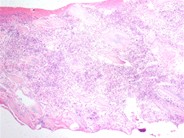

A low power view of the aspirate show a hypercellular marrow with a marked increase in megakaryocytes. Islands of erythroid precursors are also prominent.